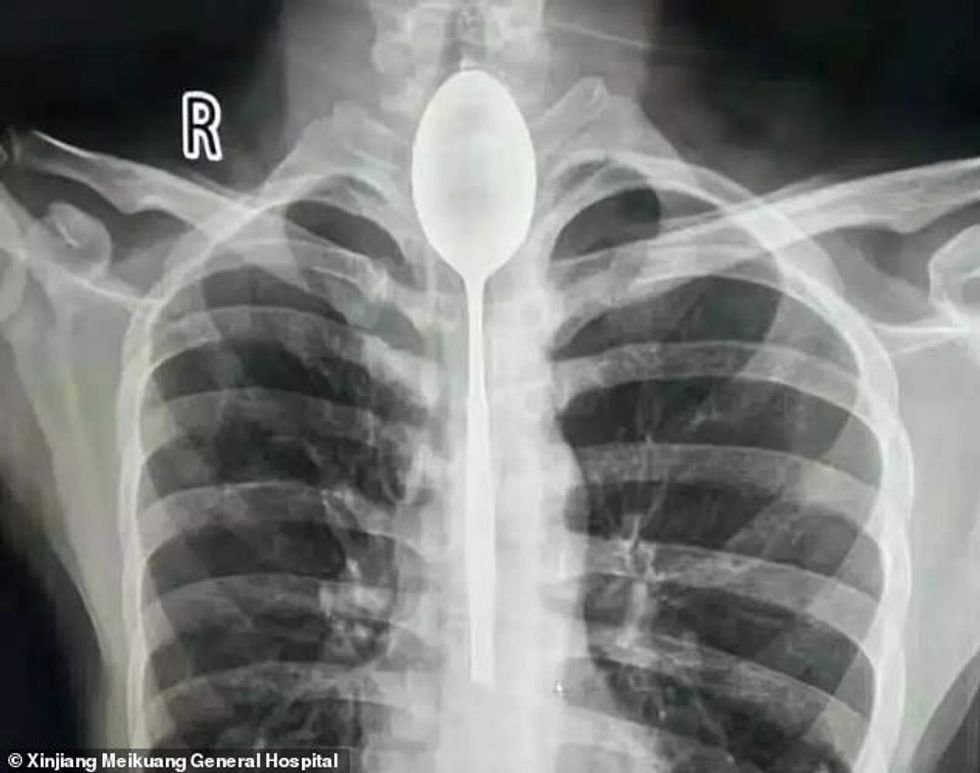

Përpiu lugën e gjatë 20 centimetra si pjesë e një basti kur ishte i dehur, e zbuloi pas një viti kur po kontrollohej për dhimbje gjoksi (Foto)

Mjekët që po e trajtonin një pacient nga Xijiang i Kinës, mbetën të hutuar kur ia gjetën një lugë metalike në fyt.

Burri 26-vjeçar e kishte përpirë atë si pjesë e një basti kur ishte i dehur, ndërsa ka harruar të nesërmen se çfarë ka ndodhur, transmeton Telegrafi.

Meqenëse nuk kishte asnjë problem në frymëmarrje apo derisa ushqehej, ai nuk kishte shkuar për kontroll për rreth një vit.

Kur filloi të kishte dhimbje gjoksi, ai shkoi për një kontroll dhe u detyrua t’i nënshtrohej fotografimit me rreze X.

“Nuk po i besoja syve, ishte një lugë në gjoks”, ka thënë njëri prej mjekëve, që intervenuar për t’ia nxjerrë me anë të endoskopisë.

Raportohet se ai e kishte pasur fytin e infektuar, ndërsa luga e gjatë 20 centimetra nuk i kishte shkaktuar ndonjë dëmtim në hapësirën ku ishte bllokuar. /Telegrafi/